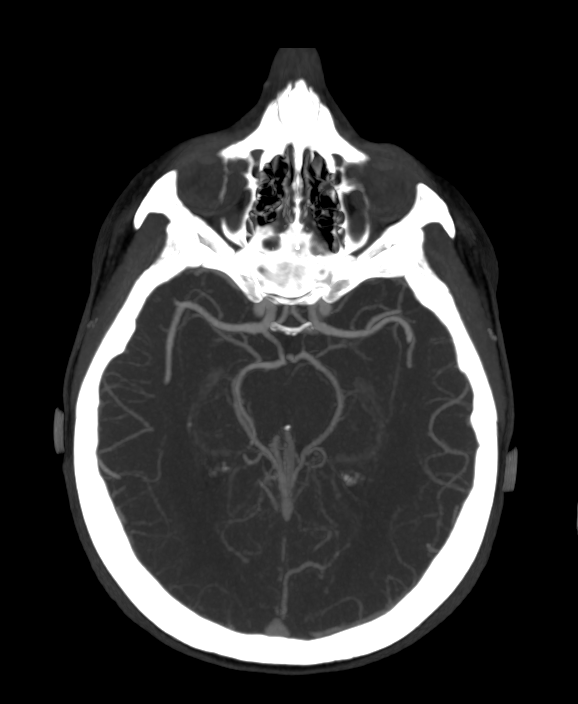

Мультиспиральная компьютерная томография сосудов головного мозга (КТ-ангиография) относится к лучевым методам исследования и применяется для оценки состояния сосудистого русла головного мозга. КТ-ангиография основана на применении рентгеновского излучения, при этом обязательно проводится контрастирование сосудов головного мозга.

Процедура заключается в том, что трубка томографа вращается вокруг анатомической зоны исследования и с помощью рентгеновских лучей делает послойные снимки, которые затем реконструируются в трехмерные изображения сосудистой системы в мельчайших подробностях. При этом по сравнению с классической ангиографией компьютерная томография не требует вмешательства в организм пациента и проводится в амбулаторных условиях.

Высокая диагностическая информативность КТ-ангиографии в сочетании с быстротой и неинвазивностью делают эту процедуру безопасной и эффективной методикой обследования сосудов головного мозга у пациентов с неврологической симптоматикой. Но особенную ценность КТ сосудов головного мозга имеет в плане скринингового обследования. Это позволяет выявлять аневризмы (расширение стенки артерии), патологическую извитость, аномалии развитии (артериовенозные мальформации), сужения просвета сосудов за счет атеросклеротических бляшек или экстравазальной, например вертеброгенной, компрессии и другие серьезные заболевания, которые долгое время могут протекать бессимптомно.

КТ-ангиография головного мозга в нашей клинике проводится на современных мультиспиральных компьютерных томографах последнего поколения TOSHIBA AQUILION. Благодаря инновационным компьютерным программам получаются детализированные снимки высокого качества и 3D-модели сосудистой системы головного мозга. При этом аппараты обеспечивают пониженный уровень лучевой нагрузки на организм пациента.

Для лучшей визуализации сосудов в обязательном порядке в вену пациента вводится йодсодержащий контрастный препарат. Контрастное вещество поглощает рентгеновские лучи, поэтому даже мелкие сосуды становятся хорошо видны на фоне окружающих тканей.